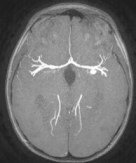

topographie :

- maladies artérielles : ci-dessous sont représentés des exemples d’anévrysmes associés à la maladie de Recklinghausen, de Bourneville, d’Alagile

nouveau-né, infection à staphylocoque doré ; hémorragie cérébrale révélatrice d’un anévrisme mycotique - anévrysmes traumatiques : en général en regard du point d’impact